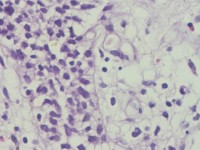

咔血3月,纤维支气管镜:右侧肺下叶基底段黏膜增生。能诊断肺部鳞状细胞癌吗?

建议:CK5/6;P63等,排除鳞癌。

鳞癌。